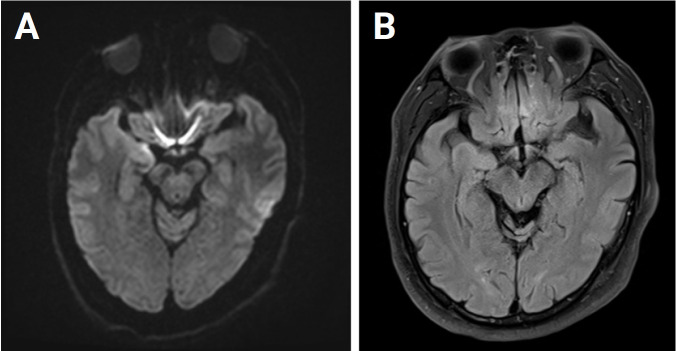

Herpes simplex encephalitis (HSE) is a common viral encephalitis that can be fatal if not adequately treated. Fever, cerebrospinal fluid (CSF) pleocytosis, and typical neuroimaging findings are commonly observed in HSE cases. We encountered a patient with HSE who did not exhibit these classic clinical features. A 63-year-old male presented with his first-ever seizure. Fever did not develop until the fourth day of admission, and neither neuroimaging nor CSF analysis revealed abnormalities. Under suspicion of autoimmune encephalitis, methylprednisolone was administered. Subsequently, when the patient developed fever, a follow-up neuroimaging study was performed and revealed abnormalities consistent with HSE. The patient was promptly treated with acyclovir, which led to a full recovery. Diagnosing HSE in patients who present without fever or CSF pleocytosis and with typical neuroimaging findings poses a challenge. Therefore, prior to initiating immunosuppressive treatment, it is crucial to closely observe patients and to conduct follow-up tests, including neuroimaging and CSF analysis.